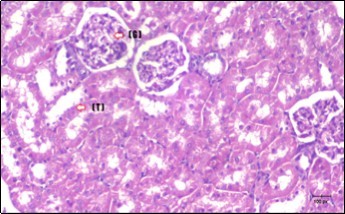

Kidney Histopathological Observations

Kidney sections of diabetic rats showed an increase in mesangial cell and matrix of glomeruli with increase in glycogen deposition and hyalinization of arterioles with thickened basement membranes of proximal and distal convoluted tubules. These changes will lead to progressive reduction in the filtration surface of the glomeruli 35. Histological examination of the kidney of the control rats showed normal structure of renal glomerular. The proximal and distal tubules were lined with normal epithelium (Figure 13). The diabetic rats showed tubular casts, inflammatory cellular infiltration and glomerular atrophy (Figure 14). Kidney of rats in groups (3 and 4) showed some glomeruli return to be normal (G). Focal tubules casts (T) in Fenugreek group and some normal tubules in the Glimepiride group with no inflammatory cellular infiltrate in both groups (Figure 15 and Figure 16). However, kidney of rats in group (5) showed normal glomerular (G), normal tubules (T) with no tubular casts (Figure 17).

Figure 13.photomicrogragh of kidney section of control rat showing normal rounded Bowman,s capsules with normal glomeruli (arrow) ,round proximal tubules (dash-arrow) and elongated distal tubules with high cuboidal cells (star) . (H&E) (40X)

Figure 14.Photomicrogragh of kidney section of diabetic rat showing a trophy of Bowman,s capsules and damage of glomeruli (arrow) and damage of distal and proximal tubules with congested blood vessels (star) . (H&E) (100Px).

Figure 15.Photomicrogragh of kidney section of treated rat with Fenugreek showing improvement of Bowman,s capsules with normal glomerular (arrow) and nearly return of distal tubules (dashed –arrow) and proximal tubules (star) (H&E) (40xX).

Figure 16.Photomicrogragh of kidney section of treated rat with Glimepiride showing improvement of Bowman,s capsules and partial improvement of glomerulir (arrow) and completely return of distal tubules and proximal tubules to the normal shape with wide urinary space. (H&E) (40X).